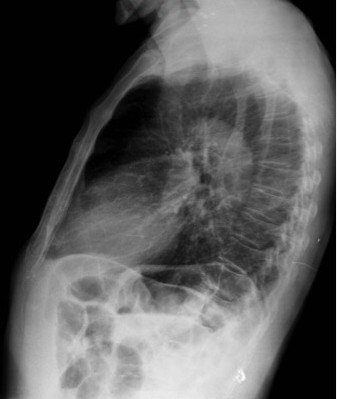

CASO: cáncer de mama. Control anual.

Hallazgos:

- Se observa un aumento de densidad con agrupación broncovascular que produce un borramiento del borde cardicaco derecho; hallazogos compatibles con atelectasia en el lóbulo medio. Véase el TC a continuación: